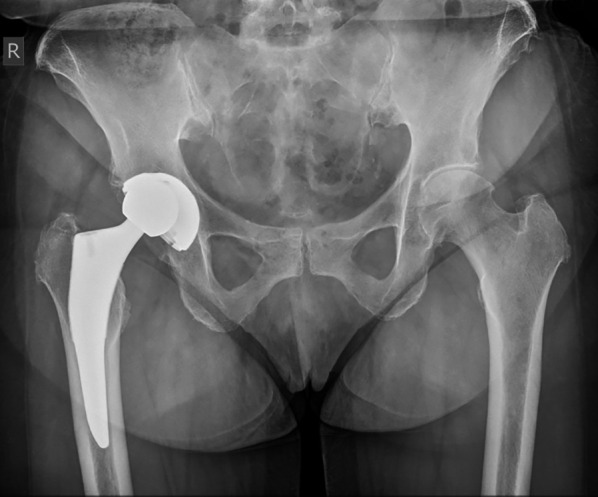

Background: Modular acetabular components for total hip arthroplasty (THA) provide intraoperative flexibility; however, polyethylene liner dissociation may occur. This study aimed to examine the incidence and causes of liner dissociation associated with a specific acetabular component design at a single centre.

Results: A total of 32 patients (0.45%) experienced liner dislocation at a mean 71.47 ± 60.10 months post surgery. Significant factors contributing to dislocations included the use of a conventional compared with a highly crosslinked polyethylene component (p = 0.049) and screw fixation (p = 0.028). Radiographic and CT analysis highlighted the importance of proper component orientation, revealing that patients experiencing dislocations demonstrated significantly lower acetabular cup anteversion angles (p = 0.001) compared with the control group. Impingement and malposition, identified in 41% and 47% of the cases, respectively, further underscored the multifactorial nature of dislocation risks.

Conclusions: While the overall rate of polyethylene liner dislocation was low, the findings of this study highlight the importance of appropriate cup placement to decrease the risk of dissociation. It further substantiates the influence of impingement and malposition in liner displacement, with increased mechanical stress exerted on the locking mechanism under adverse conditions and the potential risk increase due to screw placement.